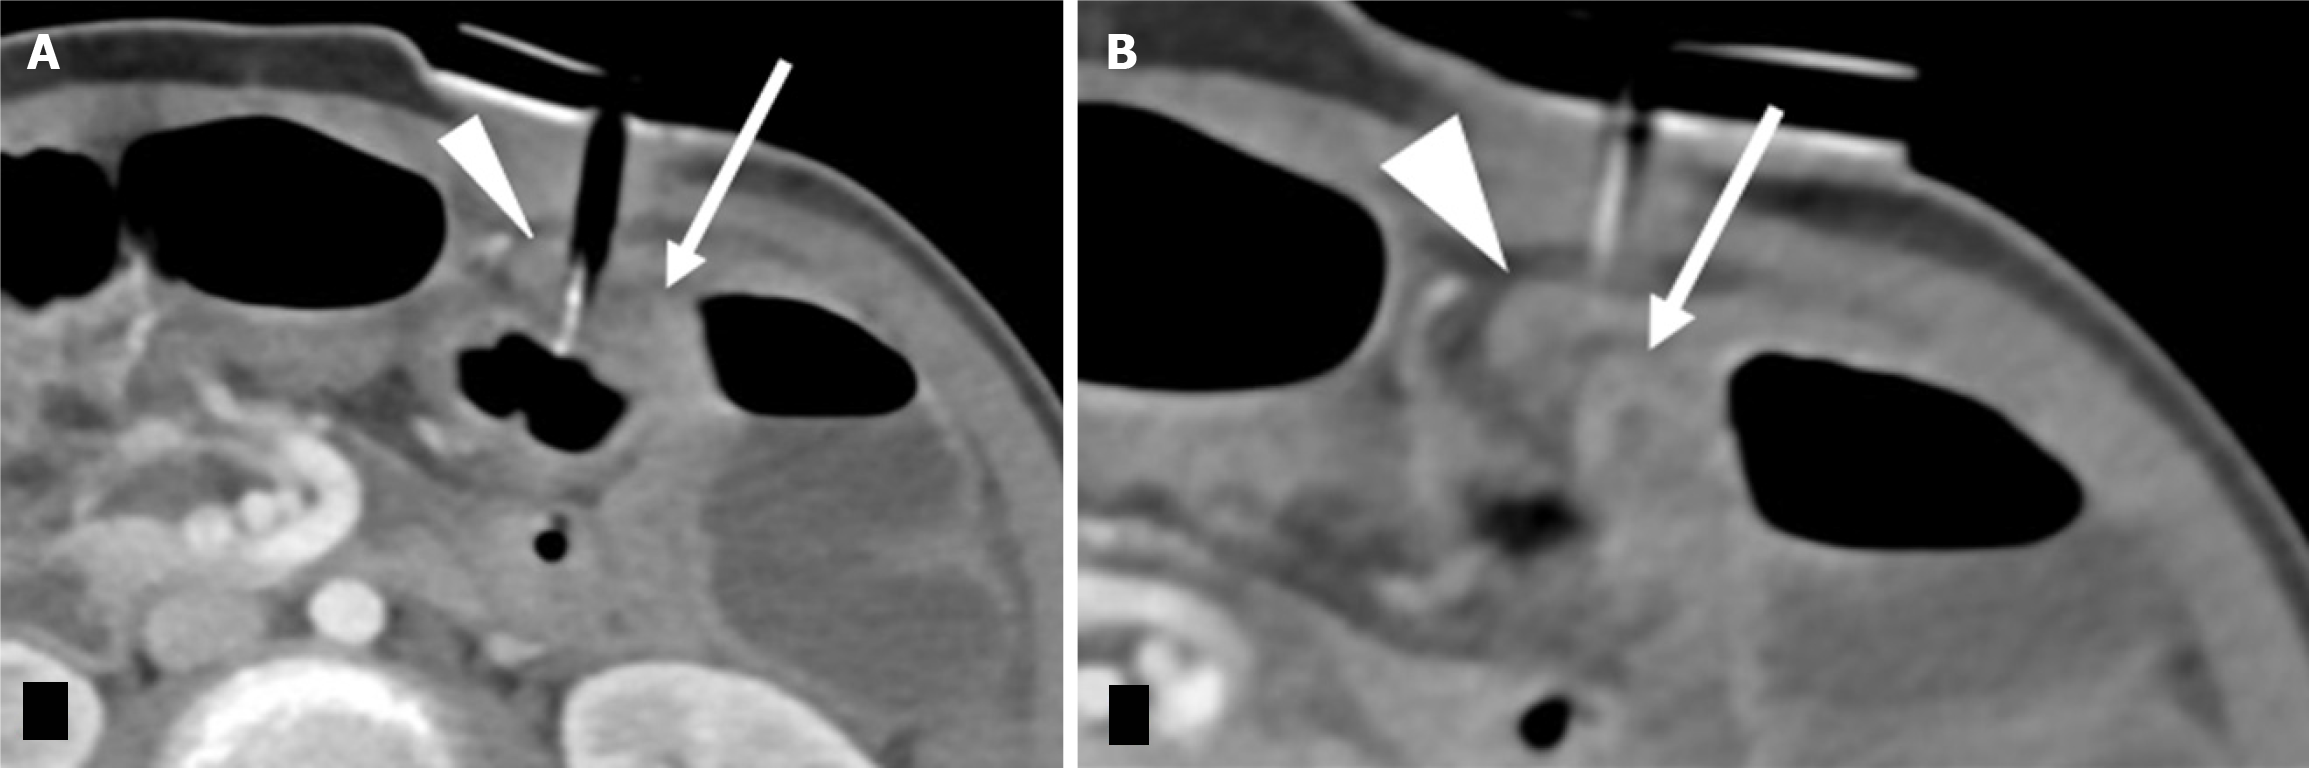

Figure 12 Abnormal gastrostomy tube placement into the bowel loops.

A 16 year old male post operative day 4 percutaneous endoscopic gastrostomy. A and B: Axial sections of the computed tomography abdomen depict the gastrostomy tube transversing the dilated small bowel (arrow) and decompressed transverse colon (arrowhead). Findings were confirmed intraoperatively along with a volvulus.